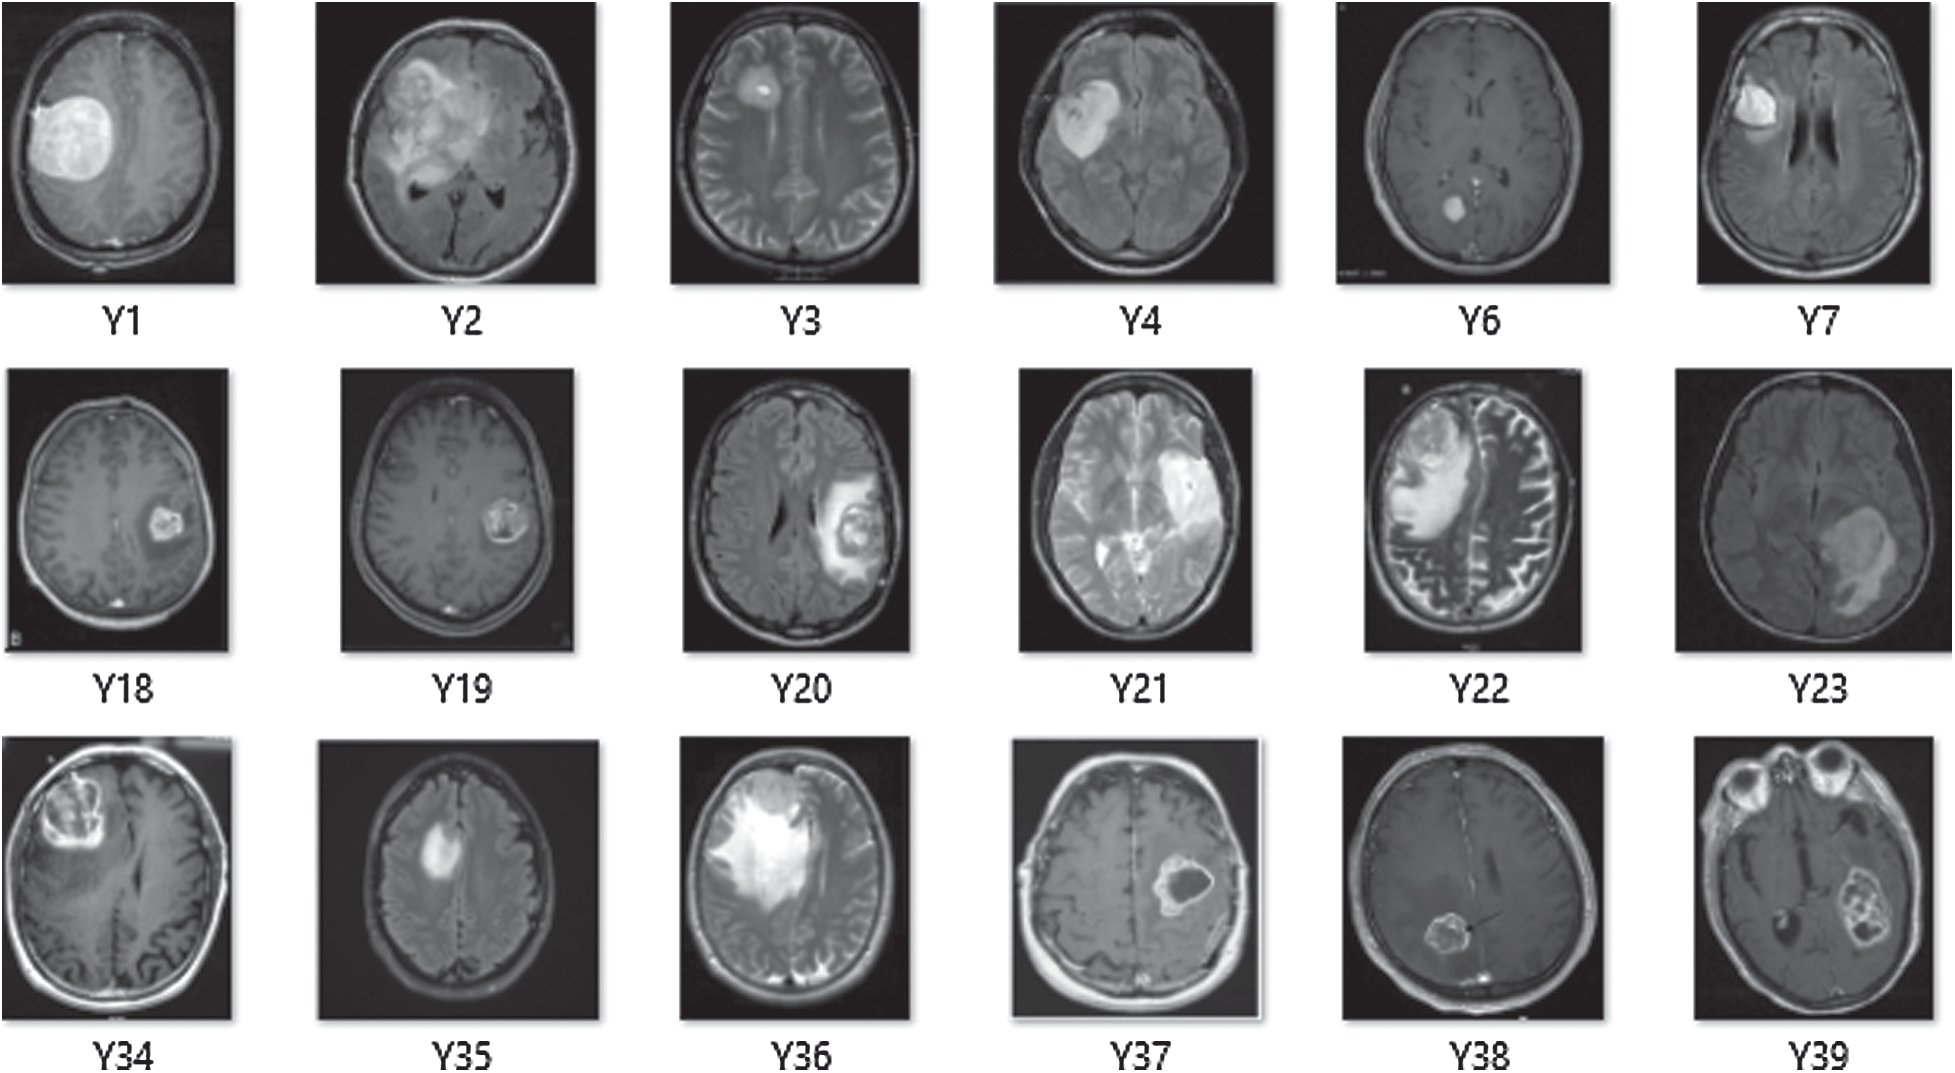

The Deep-CNN model composed of three significant parts: (i) a convolution layer, (ii) a pooling layer, and (iii) a fully connected layer. Automatic extraction of features from input images was performed by convolution layer; however, pooling layer helped in reducing dimensions of features obtained by convolution layer so that vital features are spotted for further processing, while fully connected layer flattened the features into a vector and finally it was classified into a particular label. First, the convolution layer was added to the proposed sequential Deep-CNN model. Several parameters, such as kernel size, the number of filters, padding type, activation function type, strides and bias were specified when creating a convolutional layer. Fig. 4 shows a snapshot of the Brain MRI Data.

Figure 4: A snapshot of brain MRI data